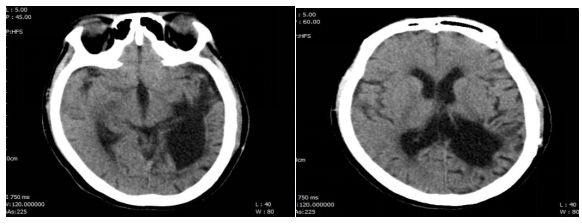

心脏超声:静息状态下心内结构及血流动力学未见明显异常。头颅CT:颅脑术后改变,左侧颞顶枕叶、基底节区脑软化灶;双侧额叶皮下、侧脑室旁多发腔梗;脑白质变性,老年性脑改变(图1)

图1  患者头颅CT

结合该患者入院头颅CT:颅脑术后改变,左侧颞顶枕叶、基底节区脑软化灶;双侧额叶皮下、侧脑室旁多发腔梗,未见明显脑水肿、颅内出血、颅骨骨折、脑挫伤、占位性病变和梗死灶,同时患者发病过程中无抽搐发作及颅内高压表现,可除外颅脑疾病所致患者意识改变,故可考虑为全身性疾病所致。该患者感染源明确,为呼吸道感染,但经过积极抗感染、抗病毒治疗后患者意识水平未见明显改善,故考虑为非感染因素可能大。患者无循环衰竭、无心功能不全表现、无中毒病史、无过度药物服用史、无外伤等物理性损伤史,故可除外因中毒、心血管疾病及物理性损伤所致意识改变。该患者既往糖尿病基础,平素未规律监测血糖,入院完善检查提示:渗透压346.27 mosm/kg,静脉葡萄糖19.85 mmol/L,钾2.44 mmol/L,钠172 mmol/L,氯137.40 mmol/L,糖化血红蛋白11.4%,甲状腺功能未见明显异常,故该患者意识改变为糖尿病高渗性昏迷所致,感染为诱发因素。